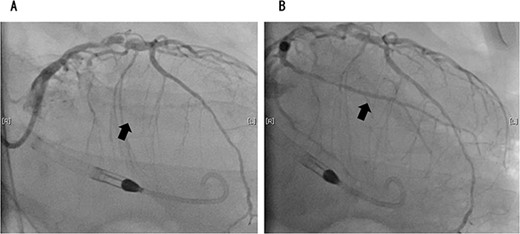

On the 2nd postoperative day, the patient experienced cardiac arrest because of a sudden drop in the saturation of percutaneous oxygen, after which his heartbeat resumed and he was intubated and placed on a ventilator. Transthoracic echocardiography showed left ventricular ejection fraction of 30%, diffuse hypokinesis of left ventricular wall motion and asynergy. Electrocardiography showed complete right bundle branch block, but no ST-segment elevation. Blood tests showed marked elevation of myocardial desensitization enzymes (CK: 362 U/L, cardiac troponin: 1143 pg/ml). Since ischemic heart disease could not be ruled out, angiography was performed. Coronary angiography revealed acute coronary syndrome with 90% occlusion of the left circumflex branch and 100% occlusion of the left anterior descending branch (Figs 3 and 4). The patient experienced shock and required VA-ECMO. However, the circulatory dynamics were unstable, and intra-aortic balloon pumping (IABP) was introduced. Furthermore, because the blood pressure could not be maintained with circulatory support from the IABP, we converted it to Impella 5.0. Assisted circulation with Impella 5.0 stabilized the patient’s blood pressure and allowed us to open the left circumflex and left anterior descending branches. VA-ECMO initially required an auxiliary flow of 1.2 L/min, which could be gradually reduced; Impella 5.0 initially required an auxiliary level of P7, which was reduced to P5 after VA-ECMO removal. VA-ECMO and Impella 5.0 were discontinued on the 6th and 8th postoperative days, respectively. He was eventually transferred by walking to a nearby facility for further rehabilitation 109 days later. One year later, the patient was recurrence-free of lung cancer.

Coronary angiography showed 100% occlusion of the left circumflex branch (A). After the procedure, the occlusion was completely released (B).